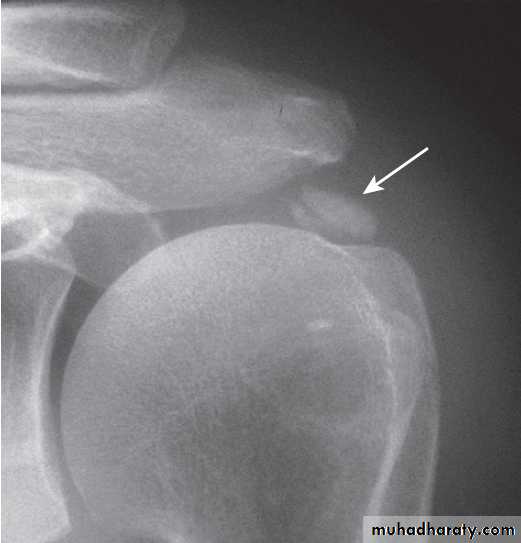

Shoulder painShoulder pain is a common complaint in both genders

> 40, and is most often due to degenerative disease of tendons in the rotator cuff .

Management is symptomatic, with analgesics, NSAID, local corticosteroid injections and physiotherapy aimed at restoring normal movement and function. Surgery may be required in debilitating symptoms in association with rotator cuff tears. Adhesive capsulitis (frozen shoulder) presents with upper arm pain that can progress over 4–10 weeks before subsiding over a similar time course. Restriction of glenohumeral movement is characteristic. In the early phase, there is marked anterior joint/ capsular tenderness and stress pain in a capsular pattern; later there is painless restriction, of movements.

Clinical findings in shoulder pain

Pain patterns around the shoulder. The dark shading indicates sites of maximum pain.